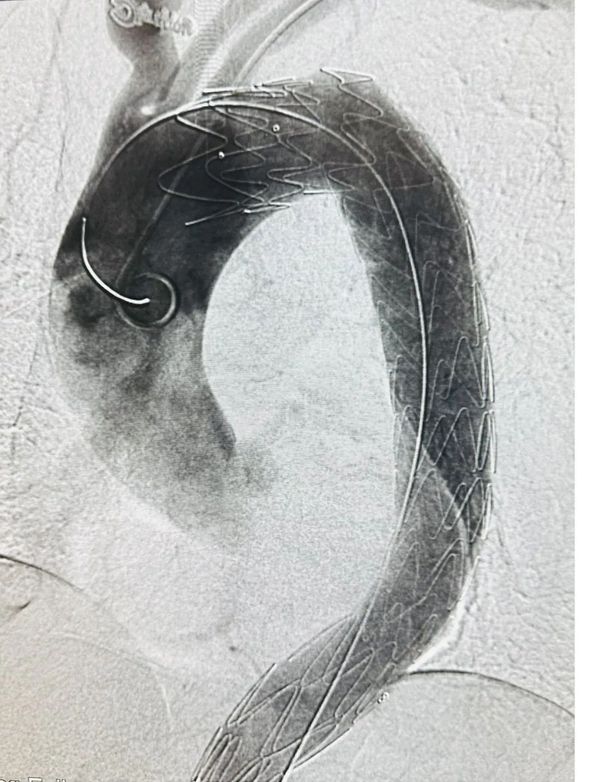

血管外科医生行胸主动脉覆膜支架置入术

术中影像